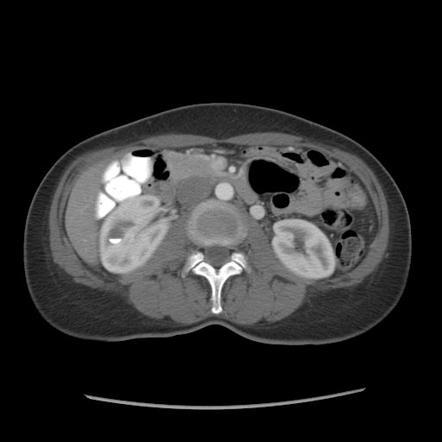

What grade?

Grade IV renal trauma

laceration involving the collecting system with urinary extravasation

laceration of the renal pelvis and/or complete ureteropelvic disruption

vascular injury to segmental renal artery or vein

segmental infarctions without associated active bleeding (i.e. due to vessel thrombosis)

active bleeding extending beyond the perirenal fascia (i.e. into the retroperitoneum or peritoneum)